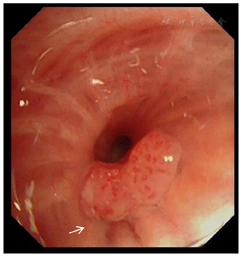

胸部CT、PET-CT、气管镜检查及病理结果(图1,图2,图3,图4,图5,图6)。

患者中年男性,慢性病程,主要表现为咳嗽、咳痰、咯血,查体右锁骨上可触及多个肿大淋巴结,质硬,固定,长期大量吸烟史,proGRP、NSE、CEA明显升高,胸部CT示右肺上叶不规则团块影,边缘分叶,多发毛刺,纵隔及右侧肺门可见多发肿大淋巴结。根据左肺下叶背段支气管黏膜活检为鳞状细胞癌,右肺上叶肺活检为肺腺癌,颈部淋巴结活检为小细胞肺癌。故本例患者肺癌诊断明确,为同时性多原发肺癌。鳞癌是在气管镜下发现,为早期阶段。腺癌的体积比较大,小细胞肺癌原发灶考虑为右侧肺门附近,如图1C、图1D、图2B中白色箭头所示,锁骨上淋巴结穿刺病理证实为小细胞肺癌转移,故在肿瘤标志物上proGRP、CEA明显升高,SCC正常,也符合其临床情况,最终分期:cT2N3M1c,Ⅳb期。